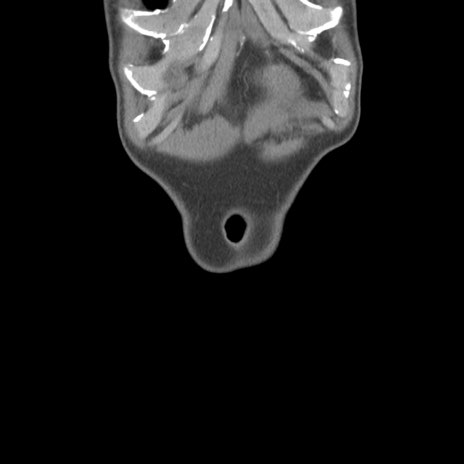

症例56 CT(冠状断像)

横断像